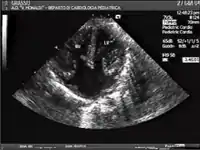

AVSDs can be detected by cardiac auscultation; they cause atypical murmurs and loud heart tones. Confirmation of findings from cardiac auscultation can be obtained with a cardiac ultrasound (echocardiography - less invasive) and cardiac catheterization (more invasive).